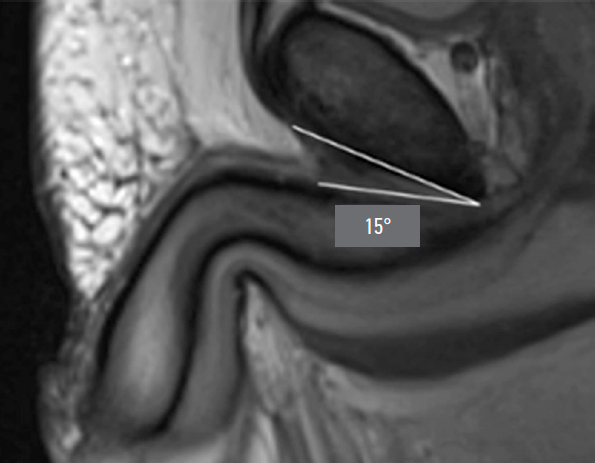

During preoperative assessment, penile length was recorded in both the flaccid and stretched states (median: 6.75 cm and 12 cm, respectively). Penile length in erection was measured by the patient at home (median: 12.5 cm). All patients underwent pelvic magnetic resonance imaging (MRI) to assess the topographic anatomy of the penile suspensory apparatus preoperatively. The following parameters were recorded: length and width of the suspensory ligament (median: 2.7 cm and 1.4 cm, respectively), thickness of the subcutaneous fat layer (median: 2.85 cm), angle of ligament divergence in the frontal plane (median: 65.8°), and the angle between the corpora cavernosa and the pubic symphysis (median: 17.42°) (Fig. 1–Fig. 5).

Fig. 5. Angle between the corpora cavernosa and the pubic symphysis.